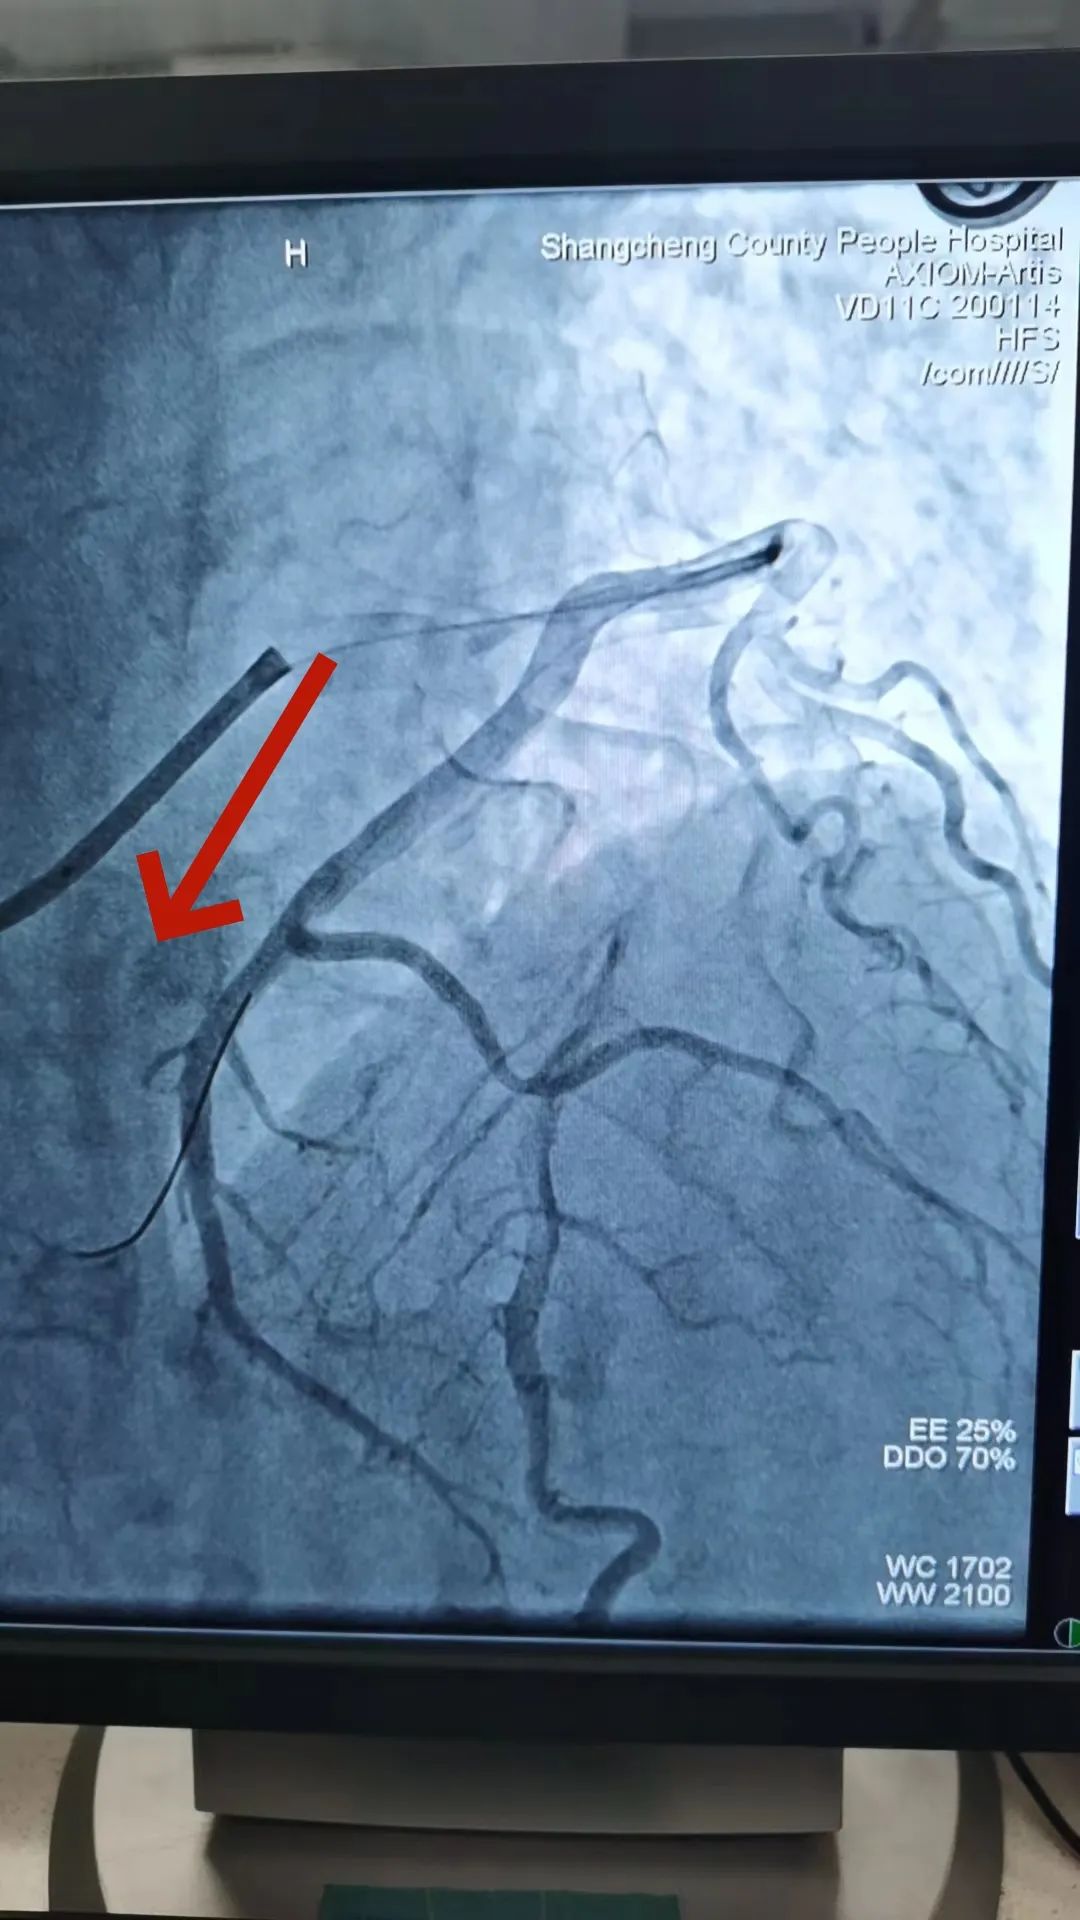

回旋支远端完全闭塞

此时,患者的胸痛症状丝毫没有缓解,复查心电图显示下壁导联ST段仍持续抬高。患者病情刻不容缓,经过短暂思考后,熊主任当机立断:尝试开通回旋支远端血管!在熊主任的指导下,刘燃医师小心翼翼的置入预扩球囊扩张回旋支远端,果然发现左旋支直径2.5mm,是右心供血功能血管。但是血管扩张后患者突然出现心率减慢、血压降低的现象,面对这种突发状况,熊主任考虑患者是再灌注后血管痉挛、心律失常,刘医生立即向冠脉内注射硝酸甘油200μg,随后患者心率、血压回升到正常。在进行重复造影后可见患者回旋支远段粗大且长,延伸至右心,再次确定回旋支远端为“罪犯血管”。经过球囊扩张手术后,血管狭窄解除,血流3级,心电图提示下壁导联明显回落,胸痛症状明显缓解,手术有效,抢救成功!